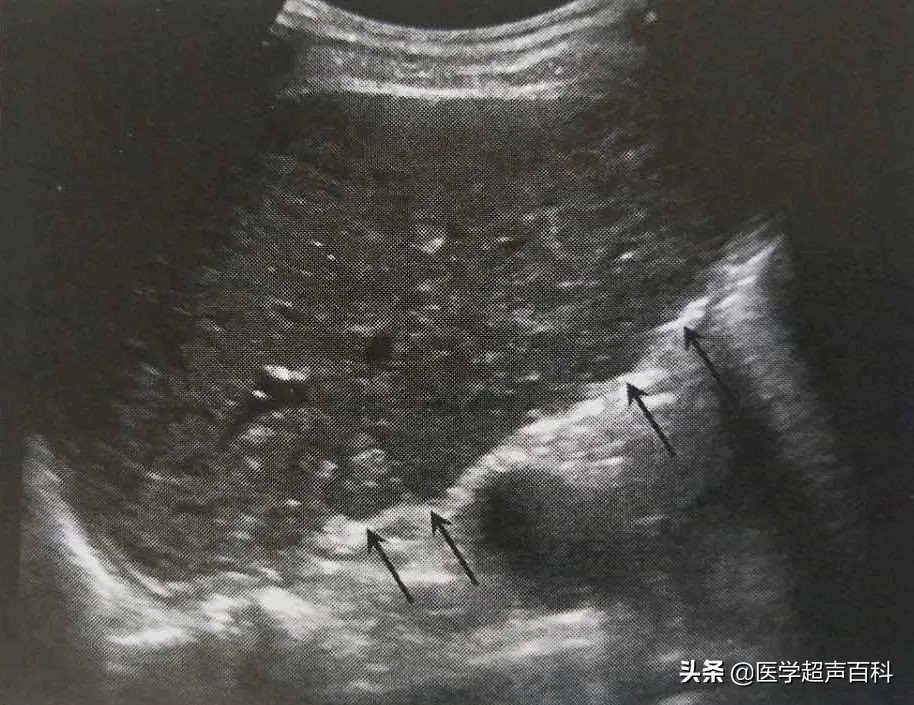

我一阵迷糊,还没反应过来,只听到一声“呕”,只见老大爷张嘴往外开始吐血(像水龙头的水一样往外涌),我一阵发蒙,这是什么情况?大概有4-5秒钟时间,等我反应过来,老大爷已经止吐。凭借经验,当时已经有所怀疑,顾不上再让他去交钱,问过他没再想吐的感觉,联系过医生后,赶紧把老大爷拉到床上,探头往上一放,果然--大量腹水,肝实质弥漫性回声改变, 肝包膜增厚,并且回声渐强,薄厚不均,肝的边缘角变钝、不规则 , 形态凹凸不平,呈现结节状,并萎缩变形 ,门脉高压,脾大。